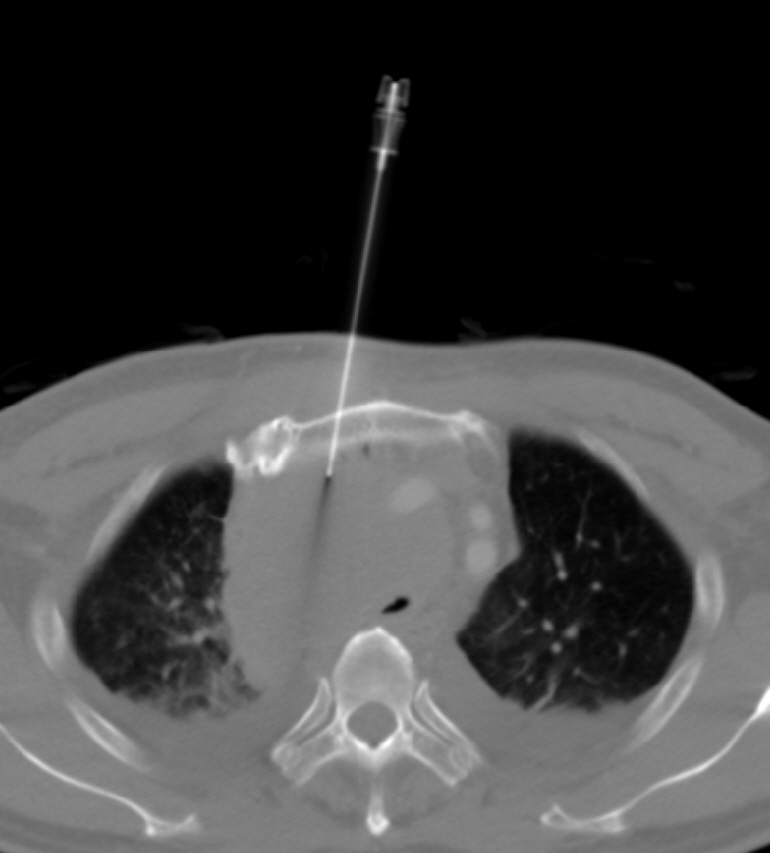

如何穿過胸骨,取得縱膈腔腫瘤?圖多,附影片。 (CT-guided biopsy: trans-sternal approach for mediastinal tumor)